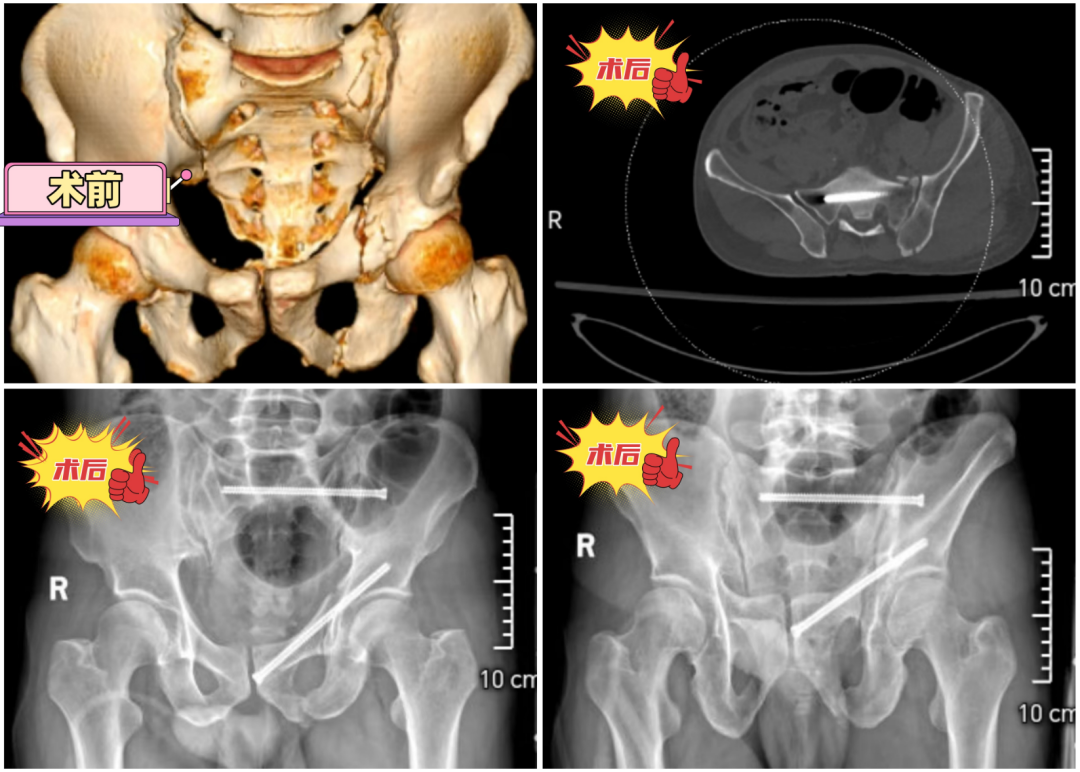

手术当天,医生仅在郭文砚臀部左侧及右侧大腿根部开了2个0.5厘米的小切口。在G型臂或C型臂透视的引导下,欧阳国新带领团队避开重要的血管和神经,将6.5mm全螺纹空心螺钉顺着骨盆的“天然安全通道”植入骨折处。

“手术出血不到50毫升,相当于一次抽血检查的量。”欧阳国新说,“与传统手术动辄上千毫升的出血量相比,患者当天就能在床上活动,1-2周即可尝试坐起;恢复行走能力的时间比传统手术缩短近一半。”

第一师医院骨科一病区现已实现"前后环一体化微创解决":通过骶髂关节螺钉固定术修复后环,用前柱螺钉或耻骨上支螺钉技术固定前环。"只要不是涉及髋臼的骨盆骨折,现在都能通过2-3个小切口解决。"欧阳国新说。